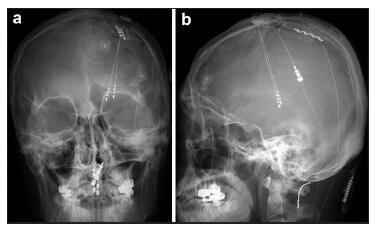

20170512094124 Figure 1 Combined thalamic ventralis caudalis (Vc) deep brain stimulation (DBS) and motor cortex stimulation (MCS) in patient #4. a An image captured from the stereotactic planning software (Framelink®, Medtronic, Minneapolis, MN) during the determination of the initial target coordinates and trajectory planning for the Vc and the hand knob in the precentral gyrus. A white arrow indicates the location of the hand knob corresponding to the hand somatotopy of the precentral gyrus. An arrowhead indicates the central sulcus. b A typical microelectrode recording during exploration of the thalamic Vc nucleus. In the area T-3.5 mm, increased firing of the thalamic sensory nucleus is observed (star), which indicates entrance into the part of the Vc nucleus corresponding to a cutaneous core of the somatotopy. c A microelectrode recording shows an abrupt decrease in the firing of the Vc nucleus (asterisk). This means that the tip of the microelectroderecording probe is located below the thalamic Vc nucleus and is within the white matter. d An intraoperative photograph showing the localization of the precentral gyrus and the central sulcus. An asterisk denotes the implantation of the Vc DBS electrode before MCS. Arrow heads indicate the marking of the course of the central sulcus over the dura mater and an arrow indicates the location of the target for the precentral gyrus. e An image showing the phase reversal (asterisk) of the somatosensory evoked potential (SEP) in the upper image. The lower image shows a motor evoked potential (MEP) response taken from the abductor policis brevis (APB) and the first dorsal interossoeus muscles (DI1) through macrostimulation of the contacts of the paddle lead over the precentral gyrus. An arrow shows the elicitation of the MEP in the contralateral hand muscles. f An intraoperative photograph showing the placement of paddle lead for MCS. The contact “2” of the paddle lead is placed on the target for the precentral gyrus. A dotted line (arrowheads) denotes the course of the central sulcus and an arrow indicate the location of the predetermined MCS target.